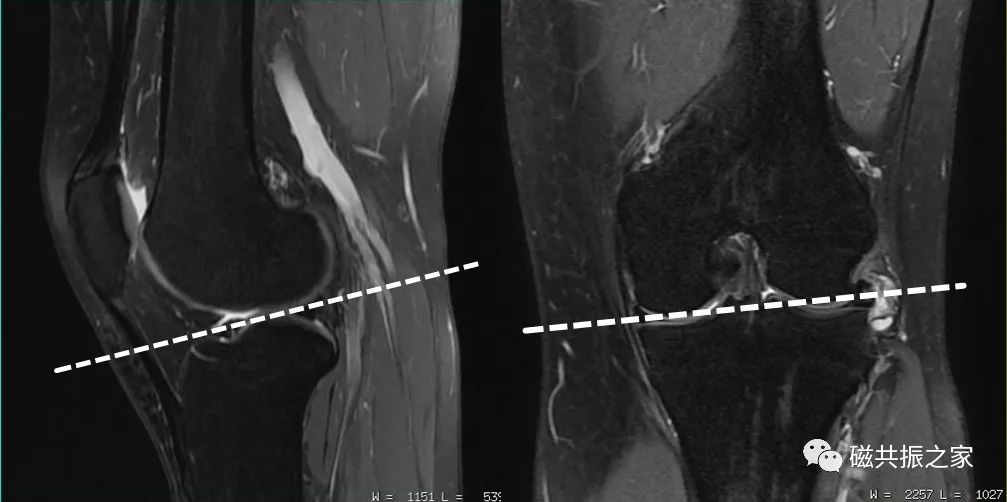

膝关节的扫描基线以股骨内、外髁后缘连线为基准,实际扫描中较常见的矢状面定位主要有两种方式:

图1:垂直于股骨内外髁后缘。

图2:平行于股骨外侧髁前缘。

膝关节扫描定位的差异主要存在于矢状位的定位中,在常规的扫描中建议采用图1的方式定位,该定位方式对90%以上的前交叉韧带都可以得到很好的显示,同时也更利于对半月板及关节软骨的评估。当标准的图1矢状面不足以评估前交叉韧带时,可补充薄层的图2斜矢状面扫描方式。

半月板作为膝关节扫描中重点观察的结构,为了更好的评估半月板的损伤类型,在定位时建议至少有一个层面要经过该半月板的损伤层面。